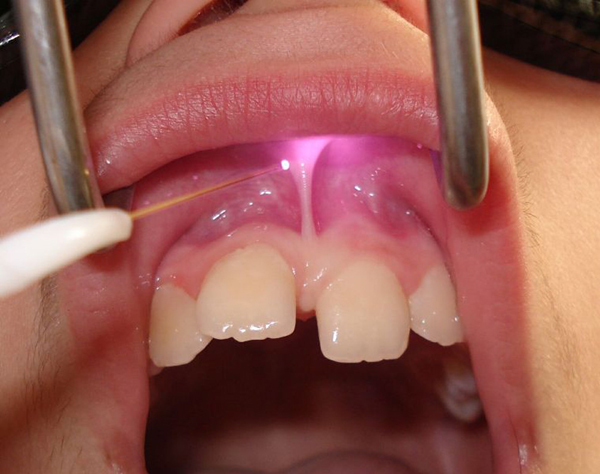

• Frenectomy : Removal of high frenal attachment with laser makes it very convenient.

• Tongue Tie : Release of tie with laser significantly improves pronounciation and function.